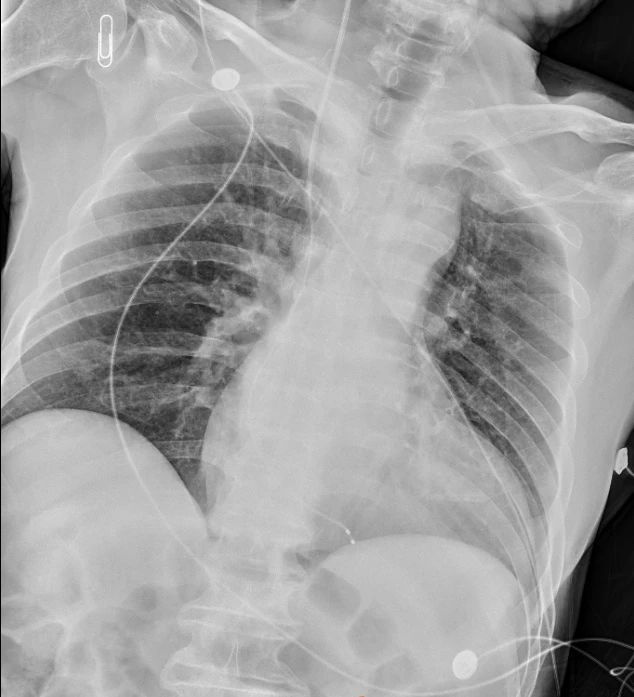

手术当日,倪大伯在6月29号一早转入了我院ICU,ICU医生团队在陈君主任医师的带领下,很快完成了漂浮电极导管床旁心脏临时起搏器的植入,术中根据监护心电波形,及植入后胸部平片,确认电极在右心室尖部嵌入良好。